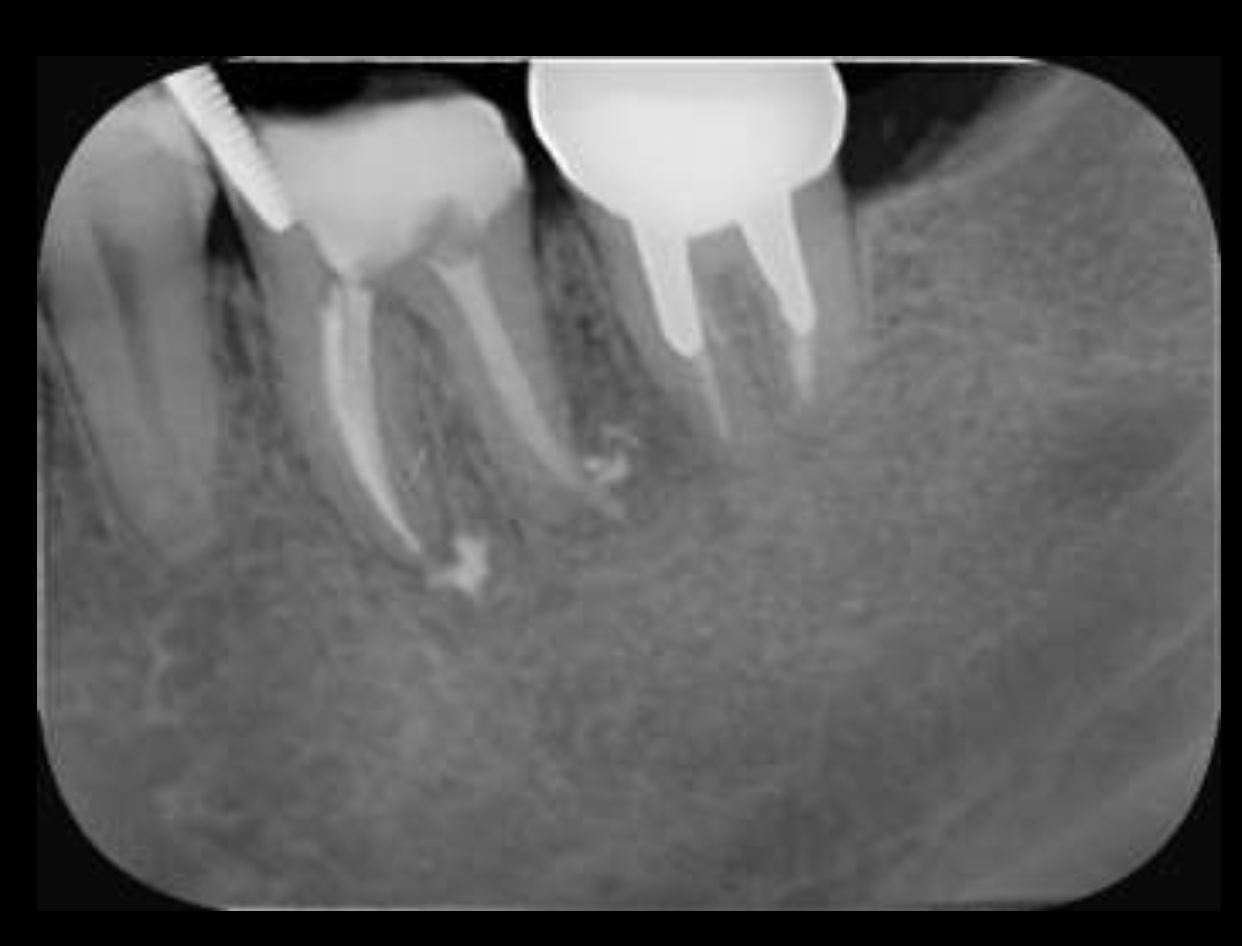

Sinus tractがある歯牙の再根管治療だ。

DB根はすでに切断されている。

が、逆根充がなされていない。

DBは根切済みだ。

Pにも病変がある。

ということは、再根管治療だろう。

ただ、予後はGuardedだ。

なぜか?根切がうまく行っていないからだ。

臨床的にDB

この後、

Sinus tractは消失した。

3ヶ月経過した。

DBの病変が小さくなっている。

Pは病変が大きくなっていうように見えるがまだわからない。

ということで、切ることだけが全てでないということを証明してくれた。